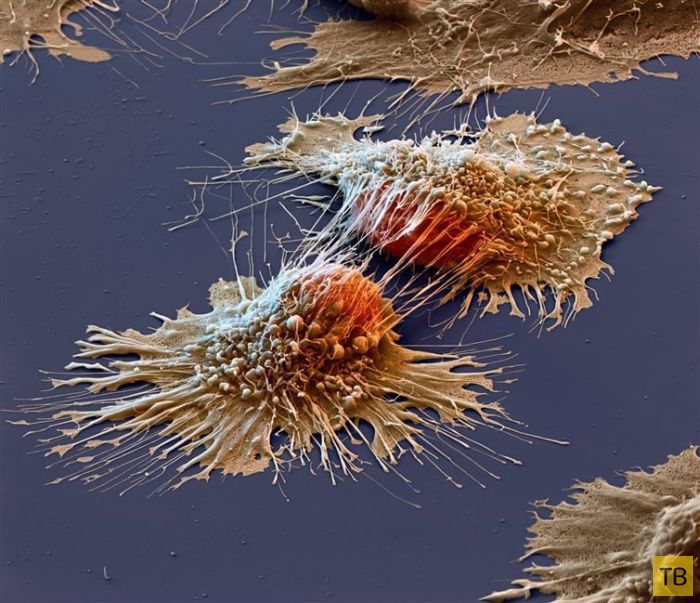

Раковые клетки под электронным микроскопом

Раковые клетки под электронным микроскопом